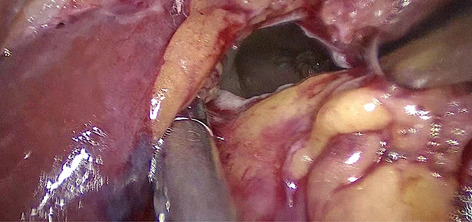

Result: The comparative analysis of the data shows a decrease in the number of presentations in ESU of AC cases during the pandemic, compared to the previous year, most often due to patients' fear of contacting the virus in the hospital environment. The median time between the onset of symptoms and the presentation in the ESU: 2020 – 14 days, 2019 – 5 days. Forms of moderate and severe AC predominated in the pandemic: GradeI—14.28%; GradeII—57.14%; GradeIII—28.57%. In 2019 GradeI—66.39%, GradeII—27.73%, GradeIII—5.88%. Laparoscopic cholecystectomy was attempted for all patients from the beginning, but the complications identified during surgery and severe forms led to a conversion rate in 2020 of 14.28%, compared to 5.88% in 2019. The severity of the cases is also observed in the postoperative complications encountered (perihepatic abscess Fig. 2. Figure 2, wound infection, bile leak; 2019—5.04%, 2020—23.21%), which required surgical reinterventions to solve them (2019: 2.52%, 2020: 10.71%). The number of deaths was significantly higher in 2020 (5.35%), compared to 2019 (0.84%).

Conclusion: Neglecting this pathology frequently encountered in ESU can lead to life-threatening complications and therefore we argue that a laparoscopically resolved cholecystectomy even in the "Covid19 era" remains the gold standard, guaranteeing the best results. Initially attempted conservative treatment may be a solution, but in the long term it can lead to severe complications and high costs.